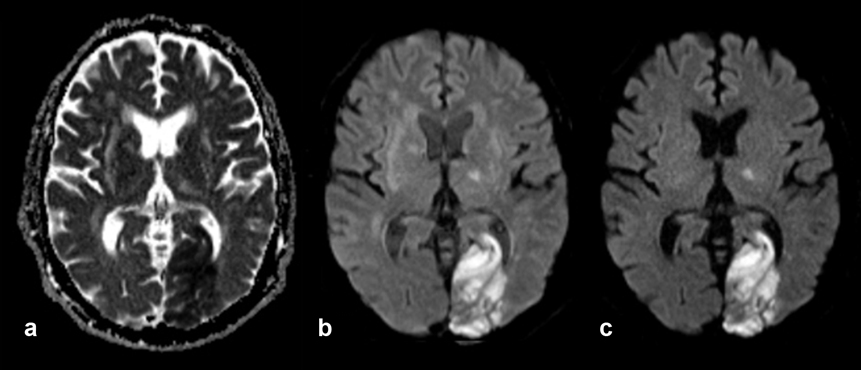

Figure 11-11:

Elderly patient with old and recent brain infarctions. New large infarction in left occipital lobe, also af­fect­ing other parts of the brain.

(a) ADC image, the area of the infarction is dark; (b) diffusion-weighted image, b = 500 s/mm²; (c) dif­fu­sion-weighted image, b = 1000 s/mm². The area of the infarction is bright.